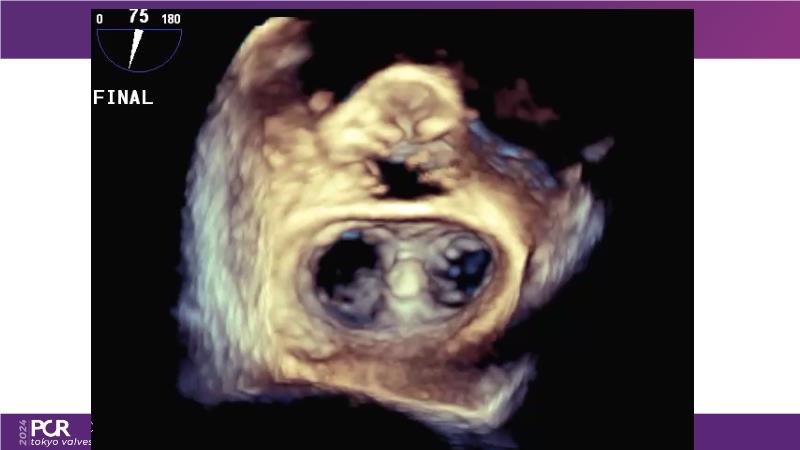

Watch this session to get an overview of a new TEER device, follow the step-by-step procedure related to initial experiences with this device for a Japanese patient with degenerative mitral regurgitation, learn about the latest data from RCT and registries, and follow discussions of challenging TEER cases!

- To learn procedural step-by-step of novel device